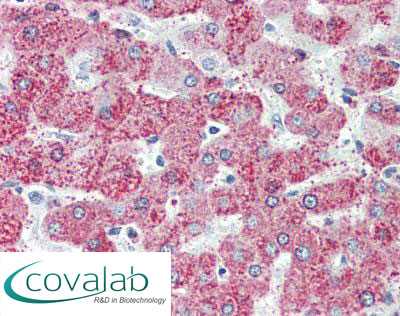

Anti-TAOK1 antibody IHC staining of formalin-fixed, paraffin-embedded human liver after heat-induced antigen retrieval.

Anti-TAOK1 antibody IHC staining of formalin-fixed, paraffin-embedded human liver after heat-induced antigen retrieval.